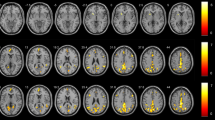

BOLD signal changes of n-back task

The BOLD signal responses of the above SWM-related ROIs changed with different n-back task loads. As the memory load increased, more brain regions were activated, and the intensity of these brain regions increased gradually (Fig. 3a,b). In the control group, all ROIs exhibited a task load effect, whereas for the HD-ESRD patients, although some ROIs were activated under three task loads, only the SFG, ACC, PCC and insula cortex exhibited a task load effect, the MFG, IFG and SPL/IPL had no task load effect. In addition, those load effects were more significant under 2- back task load.

BOLD signal changes of ROIs for the HD-ESRD group and control group under three different n-back task loads. SFG, superior frontal gyrus; MFG, middle frontal gyrus; IFG; inferior frontal gyrus; SPL/IPL, superior/inferior parietal lobule; ACC, anterior cingulate cortex; PCC, posterior cingulate cortex

Group activity differences between the three task loads

We compared the brain activation differences between three different tasks (1-back vs. 0-back condition, and 2-back vs. 1-back condition) in HD-ESRD patients and control group (Fig. 4), and also the group differences (control group vs. HD-ESRD patients group) of the three conditions (1- back vs. 0- back condition, and 2-back vs. 1-back condition) (Fig. 5). The results showed that in the 1-back vs. 0-back comparison, the degree of activation of the right MFG and IFG, right IPL, right ACC and PCC of HD-ESRD patients was lower than that of the controls, while in the 2-back vs.1-back comparison, compared with the control group, the degree of activation of the bilateral SFG, MFG, IFG, SPL/IPL and ACC of HD-ESRD patients was decreased .

Comparison of brain activity between the two groups

We found that the BOLD signal responses of the above SWM-related ROIs change with different n-back task loads. As the memory load increases, more brain regions are activated, and the intensity of these brain regions increases gradually, as the result of load effect (Callicott et al. 1999; Honey et al. 2002). Our study found that all ROIs presented a load effect in controls, whereas for the HD-ESRD patients, although some ROIs were activated under the three task loads, only the SFG, ACC, PCC and insula cortex exhibited task load effect, but not the MFG, IFG and SPL/IPL. In addition, those load effects were more significant under 2-back task. These results indicate that during working memory task, HD-ESRD patients with MCI and memory dysfunction exhibite loss of load effect in the frontal and parietal regions. Previous resting-state functional MRI studies indicate that ESRD patients have diffuse decreased ReHo values (Liang et al. 2013), and the ReHo values are significantly lower in HD-ESRD patients than in non-HD ESRD patients (Chen et al. 2015). However, few studies examine the effects of HD on cognitive function or the incidence of structural and functional neuroimaging abnormalities in ESRD patients, and most of these studies detected spontaneous neural activity by rs-fMRI (Prohovnik et al. 2007; Radic et al. 2011; Wolfgram et al. 2015). In one experimental study, Zhang et al. (Zhang et al. 2013) demonstrate predominantly decreased gray matter volume in the following brainareas: bilateral occipital lobes, bilateral lingual lobes, bilateral calcarine, precuneus/posterior cingulate cortex/cuneus, bilateral fusiform, right frontal lobe, bilateral superior temporal gyri, bilateral temporal pole, left hippocampus/ parahippocampus, left insula, bilateral uncus, right parahippocampus, right amygdala in ESRD patients, which is associated with neurocognitive dysfunction, and serum urea level may be a risk factor for decreased gray matter in ESRD patients. Hsieh et al. (Hsieh et al. 2009), who characterize and compare regional differences in anisotropy in patients with ESRD and in healthy controls by using diffusion-tensor imaging to understand the effect of ESRD and hemodialysis on the microstructures of white matter, reporte that the ESRD group have significantly lower FA values in all regions (including the bilateral frontal, parietal, occipital and temporal white matter, and the genu and splenium of corpus callosum) than the control group. In our study, some the fMRI deactivation regions are same to these brain structural changes in the obove studies, we also find that both serum creatinine and urea levels is negatively correlated with the percentage of BOLD signal change both in the frontal cortex and parietal lobule. It is possible that HD procedure is likely to cause these abnormalities (Bossola et al. 2011; Chen et al. 2015; Odagiri et al. 2011). HD can lead to the transfer of body fluids and electrolytes, leading to edema and lowering of cerebral blood pressure and cerebral perfusion, which may have adverse effects on the cognitive function of HD patients (Drew et al. 2013; Hata et al. 1993). Hermann et al. ‘s results suggest that HD may disrupt cerebral blood flow and oxygen saturation, leading to cognitive impairment (Hermann et al. 2014).

Our study indicates that the right MFG and IFG have lower activation in HD-ESRD patients when comparing the 0-back vs. 0-back task between the two groups (Control Group > HD-ESRD Group), whereas for 1-back vs. 1-back task, the bilateral SFG and MFG, right IFG, IPL and ACC, PCC and left insula have lower activation in HD-ESRD patients, and for 2-back vs. 2-back task, the bilateral SFG, MFG IFG, SPL/IPL and ACC, PCC and insula show less activation in the HD-ERSD patients. These results are consistent with several previous studies (Callicott et al. 2000; Perlstein et al. 2001). Thus, the load effect of a BOLD signal can be used as an effective indicator to judge whether there is working memory dysfunction. The prefrontal cortex (PFC) and ACC play an important role in working memory processing (Leung et al. 2005; Rowe et al. 2000). The PFC is considered as the consolidation and operation center of neural mechanism in working memory, and is responsible for the meta-processing of spatial position sequence, including attention and inhibition, as well as the management and integration of memory information (Funahashi 2006). The parietal lobe is the main place for storage of spatial information (Berryhill and Olson 2008). Some studies suggest that the precuneus plays a particularly important role in maintaining visual working memory and visual spatial storage (Diwadkar et al. 2000). Preclinical studies and biopsy findings suggest that the hippocampus mediates working memory (Zhang et al. 2015), which is also confirmed in our study showing that lower activation in the right precuneus and bilateral parahippocampal gyrus is associated with worse cognitive function in 2-back task.